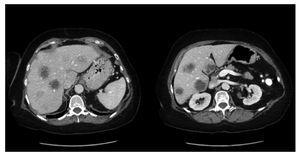

A 65-year-old woman with a remote history of breast cancer was admitted to the hospital with a three week history of weakness, fatigue, nausea, anorexia, and two episodes of fever up to 38.5°C. There was no history of GI bleeding, recent abdominal surgery, diverticulitis or recent travel outside the United States. On exam, temperature was 37.1°C, heart rate 102 beats/min, respiratory rate 20 breaths/min, blood pressure 128/82 mmHg. On palpation, the abdomen was soft with mild right upper quadrant tenderness. The liver edge was tender and palpable 5 cm below the costal margin. Laboratory tests revealed leukocytosis (26.4 x 109/L, 82% neutrophils), platelet count 592 x 109/L, C-reactive protein 250 mg/dL, serum albumin 2.5 g/dL, blood glucose 97 mg/dL, serum creatinine 0.9 mg/dL; liver biochemistries, including aspartate and alanine aminotransferases, bilirubin and alkaline phosphatase were all normal. Chest x-ray was unremarkable. Echocardiogram was unremarkable and negative for evidence of endocarditis. Contrast enhanced abdominal CT demonstrated multiple large low density lesions with irregular walls located in both hepatic lobes. There were at least 8 lesions, with the largest measuring 4 cm in diameter and located at the dome of the liver. These findings were suspicious for metastatic disease and less likely for hepatic abscesses (Figure 1). There were no abnormalities of the pancreas, spleen, kidneys, adrenals, small bowel or any segment of the colon. Indium leukocyte scan was subsequently done with no definite abnormal focal tracer uptake in the liver to suggest infection. MRI/MRCP of the liver revealed multiple hepatic lesions, measuring up to 4 cm in diameter with imaging appearance favoring abscess, however could not exclude necrotic or infected metastases. Ultimately, the patient underwent ultrasound-guided biopsy of the liver lesion with pathology findings of fragments of purulent exudates. The liver pathology showed non-specific changes and no malignancy was recognized. Multiple stains for microorganisms were negative, amoeba and parasites were not identified and blood cultures were negative. An attempt to leave a percutaneous drainage in the larger liver abscesses was unsuccessful due to the very thick nature of the pus within the lesion, and only one mL of pus was obtained and sent for culture. Further examination with colonoscopy revealed a penetrating foreign body at 25 cm from the anal verge. The foreign body was removed with a polypectomy snare and was confirmed to be a chicken bone (Figure 2).

Figure 1.Abdominal CT scan with contrast demonstrating multiple large, low density lesions with irregular walls localized in both hepatic lobes.